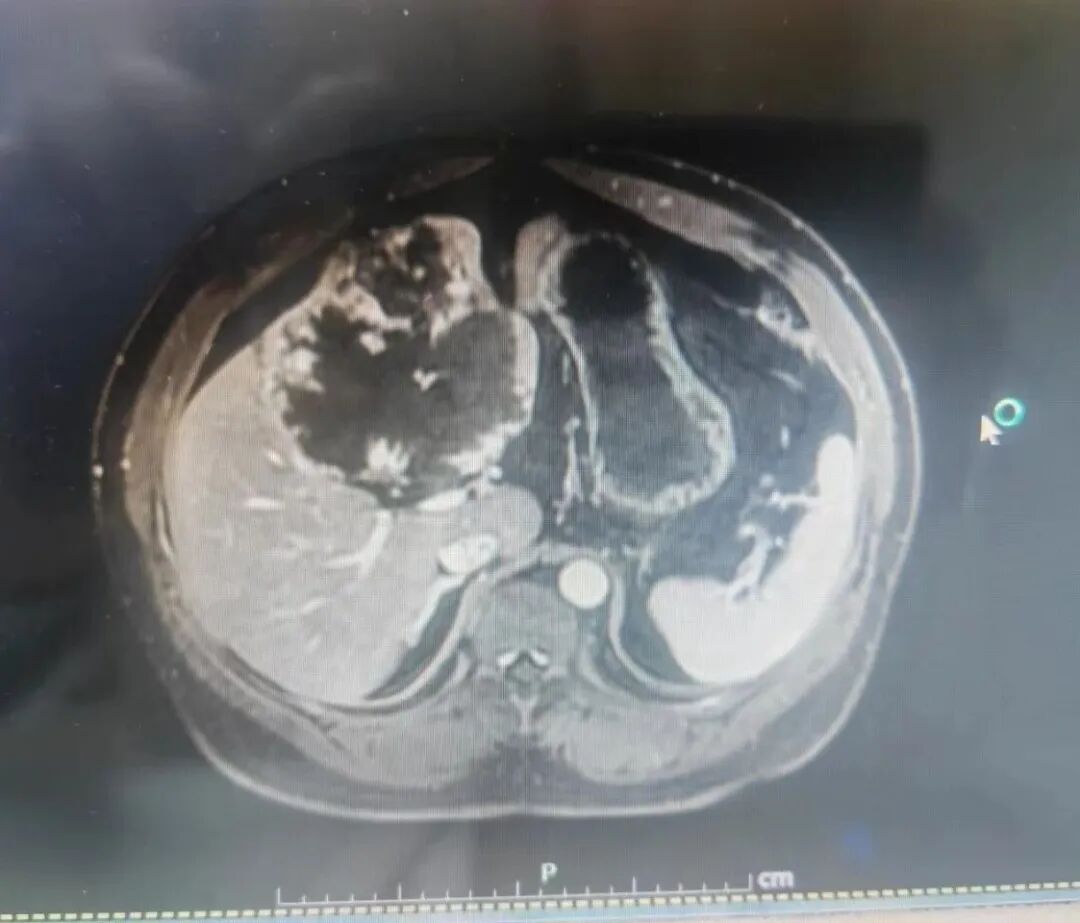

近日,沧州市中心医院肝胆外科柴伟主任团队成功完成一例高难度腹腔镜巨大肝血管瘤切除手术,以精湛技术再次突破肝胆外科微创手术的极限。患者肝内瘤体直径达13×14厘米,如成人拳头般大小,手术风险极高,传统开放手术创伤巨大。

肝血管瘤虽是良性肿瘤,但瘤体超过10厘米即被定义为“巨大”,其手术切除一直是肝胆外科领域的复杂难题。这位患者瘤体达13×14厘米,不仅体积庞大,血供丰富,且位置紧邻重要血管和胆道,术中稍有不慎便可能引发难以控制的大出血或损伤关键结构,风险极高。